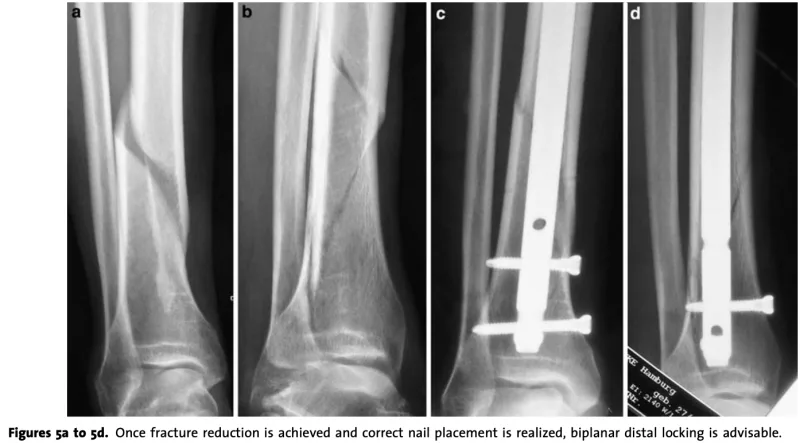

引用元:Ruecker AH. Distal tibial fractures: Intramedullary nailing. Eur J Trauma Emerg Surg. 2–9. 35.

本日の手術は, 後期高齢者の脛骨骨幹部骨折に対する髄内釘固定術.

脛骨の中央より足関節寄り(遠位骨幹部)と腓骨遠位部の粉砕骨折を伴うケースでした.